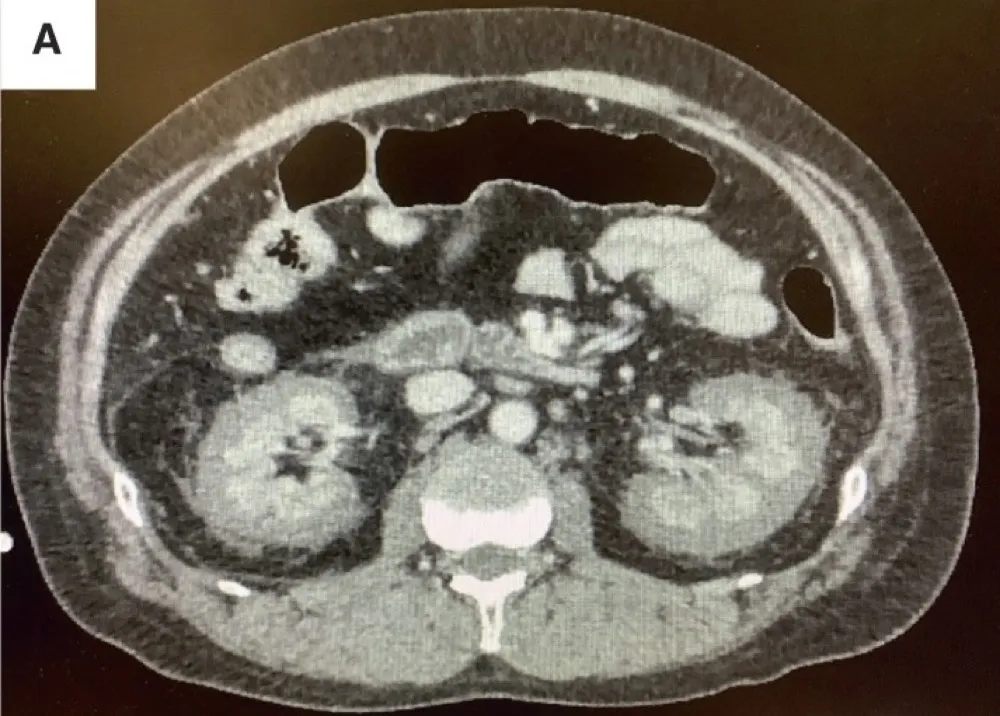

DRC indeterminada ou você esqueceu de fazer o básico? Veja tudo aqui

DRC “indeterminada” raramente é falta de diagnóstico — quase sempre é falta de método. Tempo de evolução, urina bem avaliada, USG renal e história clínica dirigida mudam conduta e evitam erros comuns na prática nefrológica.

IRA + Icterícia: Um Caso que Exige Investigação Detalhada